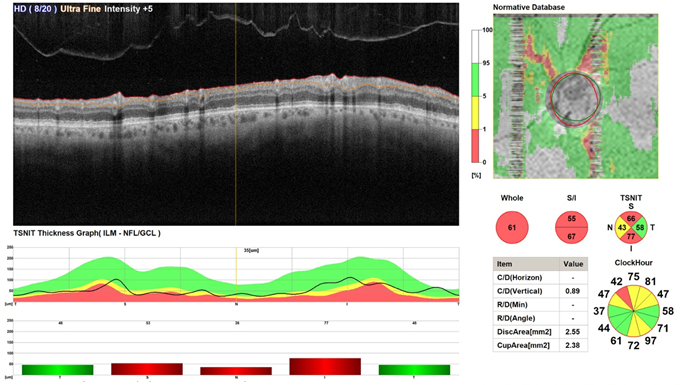

The OCT of the optic disc in map and circle scans shows reduction of ganglion cell complex volume along with reduction of RNFL thickness in superior, inferior, and nasal to the optic disc.

OCT of the optic disc map and circle shows no significant changes in term of ganglion cell volume and thickness of the RNFL (Figure 3).

Figure 3 Shows OCT scans every 4weeks of the optic nerve and RNFL from baseline toward 8weeks follow up showing no significant changes.